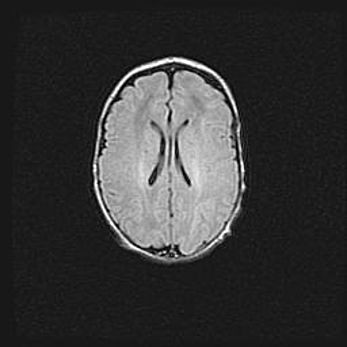

Церебральная ишемия II.

Возраст: 5 дней

Вес: 3400 г

Пол: женский

Окружность головы: 35 см

Срок гестации: 39 недель

Церебральная ишемия – это заболевание, характеризующееся недостаточностью (гипоксией) либо полным прекращением (аноксией) снабжения мозга кислородом по причине закупорки одного или нескольких сосудов. Это приводит к  что метаболическим расстройствам различной степени тяжести в тканях головного мозга, развитию коагуляционных некрозов и гибели нейронов.